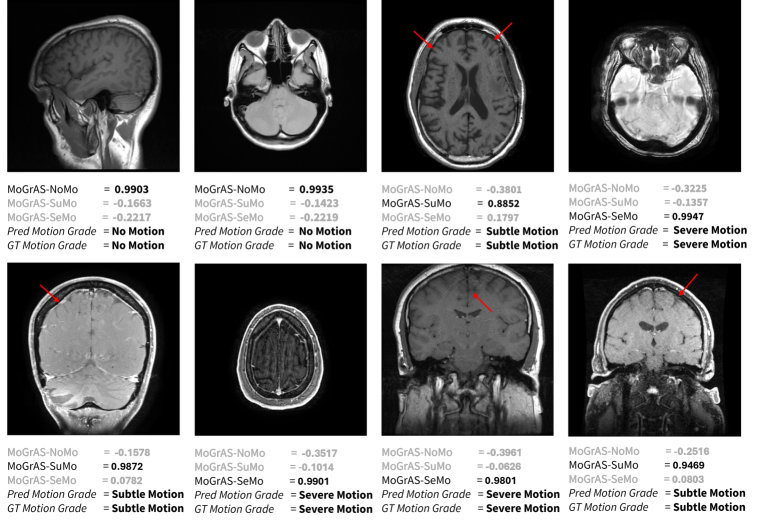

Figure 5: Examples of MR slices with predicted motion grades and associated grade affinity scores from the proposed framework. Each image displays the predicted grade, ground truth grade marked by the technologist and associated 3 grade affinity scores.

3.4 Qualitative Examples

Figure 5 presents MR slices along with the corresponding predicted motion grade and the MoGrAS for each motion grade. In all examples the MoGrAS for the predicted category is higher than the MoGrAS for other motion grades, but the extent of same varies across cases. Cases with clear motion artifacts exhibit elevated MoGrAS-SeMo, while MRI scans without visible motion artifacts exhibit higher MoGrAS-NoMo. Similarly, MR images with subtle motion artifacts have been identified and scored appropriately.